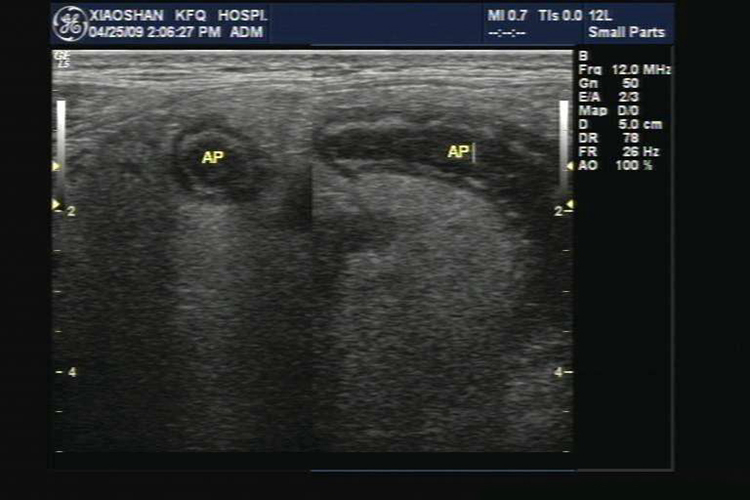

阑尾炎患者的超声表现为阑尾增粗,出现“靶环”征,以及阑尾壁层次不清等,间接征象如阑尾区低同声团、超声麦氏点征阳性、回盲部淋巴结肿大、腹盆腔积液,阑尾腔内偶见粪石强回声等,阑尾壁及其周围血流丰富。